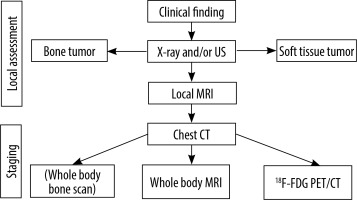

Whole-body MRI enables the investigation of systemic spread of malignant neoplasms and is cautiously recommended in their diagnostics and staging in children as well as in the surveillance in cancer predisposition syndromes [36]. In our centre WB-MRI is used routinely in children with ES, RMS, neuroblastoma, and Langerhans cell histiocytosis. The diagnostic and staging scheme for suspected malignant bone or soft tissue tumours is shown in Figure 11.